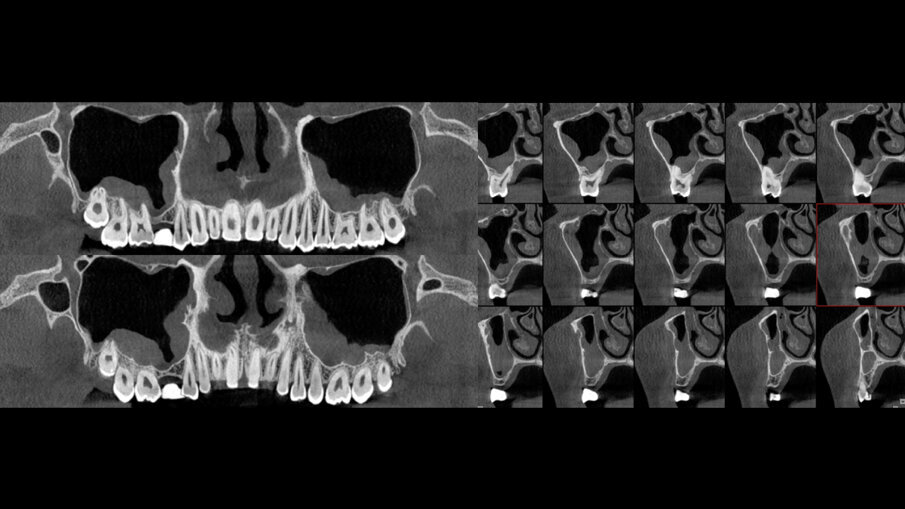

Sešití bylo provedeno jednoduchými stehy za použití nevstřebatelných stehů (hedvábí č. 4/0) (obr. 4). Pacientka podstoupila systémovou antibiotickou, analgetickou a protizánětlivou léčbu po dobu osmi dní. Co se týče pooperační péče, byla pacientka instruována, aby dodržovala přísnou ústní hygienu. Šest měsíců po zákroku byl pořízen a vyhodnocen pooperační sken z CT a byla na něm patrná tvorba nové kosti ve výšce 12 mm kolem celého těla a apexu implantátu (obr. 5).